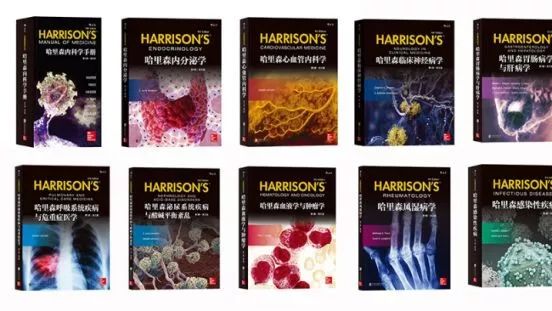

全球销量超过100万册的“哈里森”英文版,低价时间只剩三天! 医学界影像诊断与介入频道 · 公众号 · 医学 · 7 年前 · |

享誉世界的“哈里森”英文版,今天低至68折! 医学界影像诊断与介入频道 · 公众号 · 医学 · 7 年前 · |